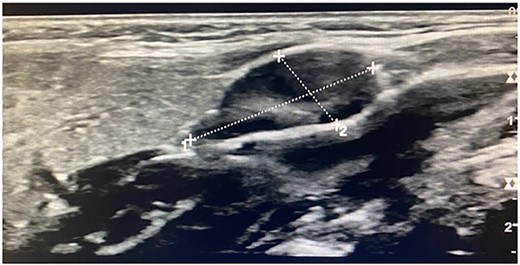

Imaging examination of the patient was done by performing CT and US. US Doppler showed a right dilated internal jugular vein (Fig. 2). The CT scan confirmed this finding, which suggested internal jugular vein phlebectasia (Fig. 3).

Imaging examination of the patient was done by performing CT with contrast and US. US Doppler showed a right dilated internal jugular vein during coughing and the valsalva maneuver (Fig. 5). CT showed a wide right internal jugular vein (Fig. 6). Both cases managed conservatively with follow-up and no surgical intervention as they did not have any complication or cosmetic concerns.